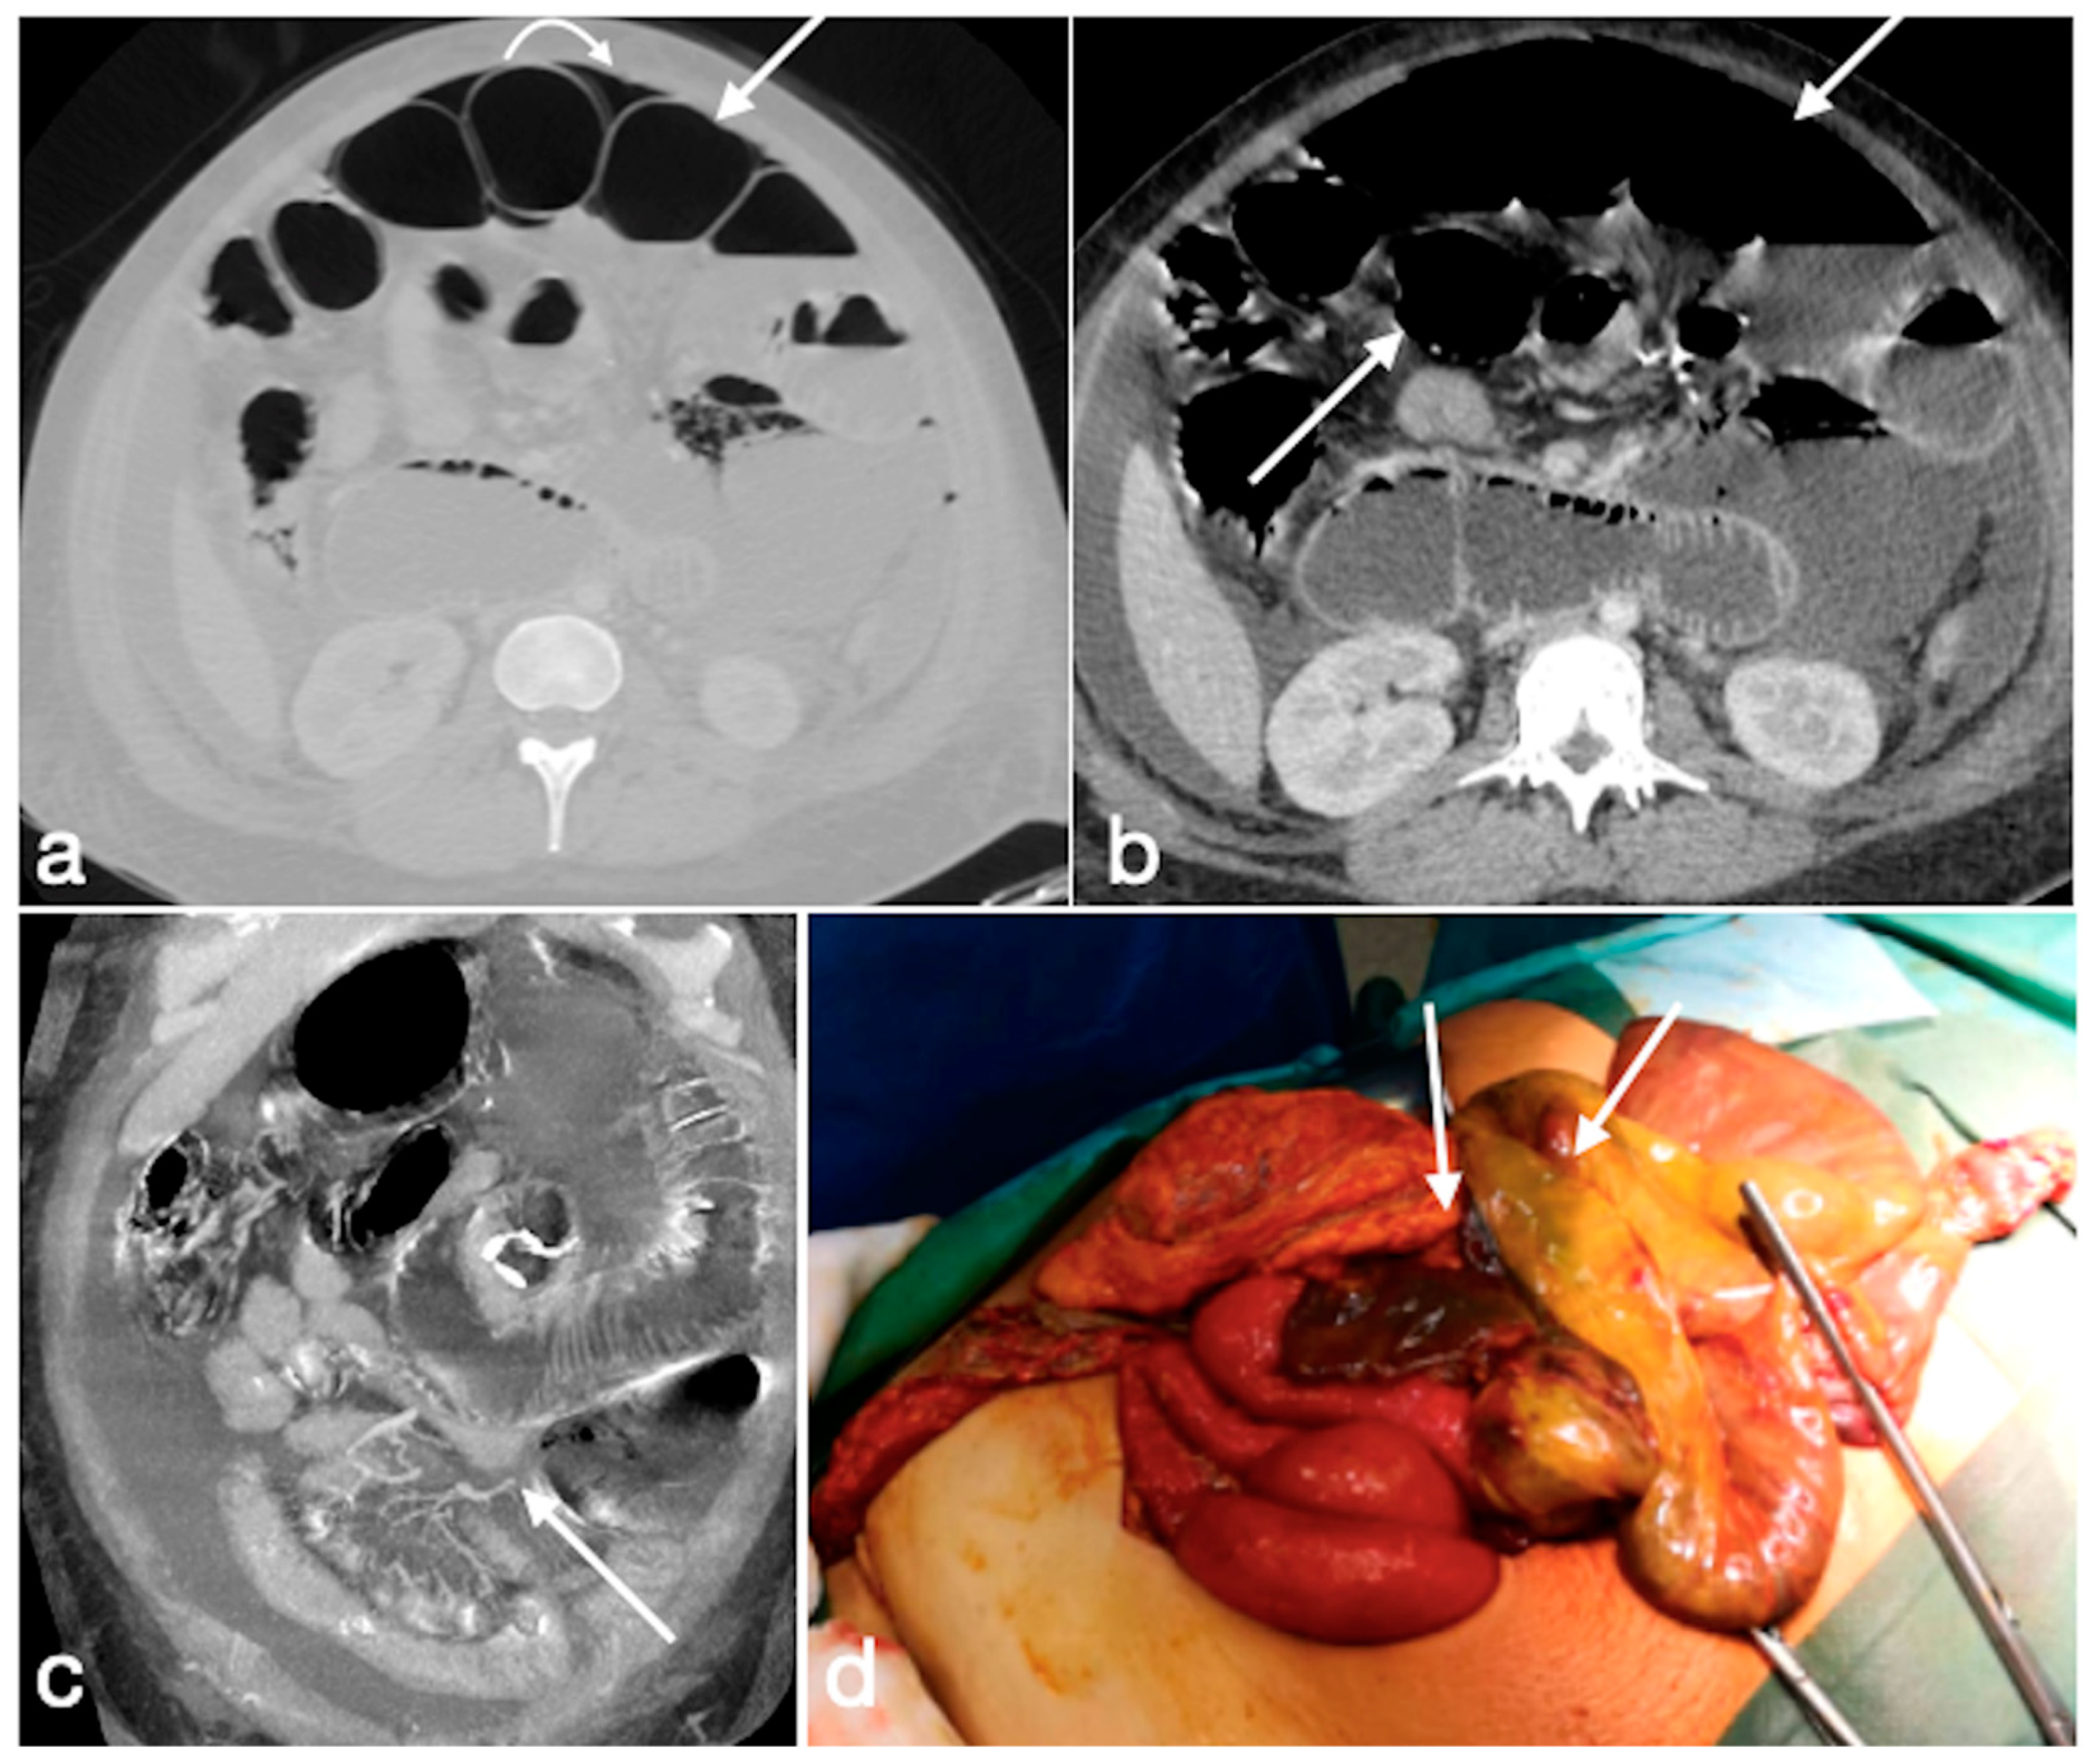

Figure 16. Internal hernia with bowel necrosis after cesarean delivery. A 37-year-old-female patient complaining of abdominal pain, fever, and constipation early after cesarean delivery. Note the presence of intraperitoneal free air (a, axial view, curved arrow), overdistension of a small bowel loop with thin wall, some of them with barely noticeable enhancement (a,b, straight arrows), and the convergence of bowel, mesentery, and vessels of the closed loop at the hernia orifice (c, coronal view, straight arrow). The prompt volume reduction of the lower abdomen is probably due to the delivery, which solicited the bowel herniation. The patient underwent prompt surgery confirming the CT diagnosis and leading to bowel resection due to necrosis (d, straight arrows, bowel loops in different stages of ischemia/infarction). Image courtesy of Dr. Michele Lanza, Dr. Antonio Brillantino and Dr. Maurizio Castriconi Department of Emergency Surgery, “A. Cardarelli” Hospital, Naples, Italy.